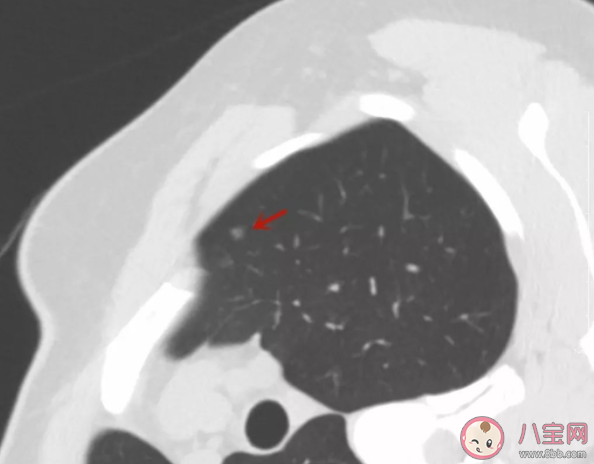

肺癌可能长成肺结节的样子,也可能是别的样子(大肿块等)。通常情况下,长成肺部小结节样子的肺癌,是癌症中恶性程度比较低的。

如果结节是实性的,大于8mm,那要谨慎抉择,因为如果是肺癌,将有可能快速进展。

如果结节是磨玻璃的,不要慌张,至少间隔三个月随访一次是必要的。

如果结节位置比较深,位于肺门附近或者肺叶中间,手术要比较慎重,因为大多数需要切除一个肺叶。